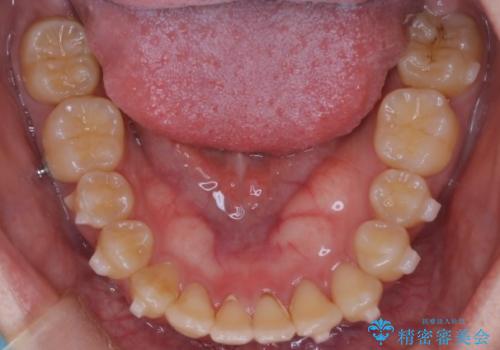

前歯の開咬とシザーズバイトを改善|インビザライン矯正

- 前歯が噛み合わない(開咬)ことと、奥歯の噛み合わせが交叉している(シザーズバイト)ことを改善するため、インビザラインによるマウスピース矯正を計画しました。精密な口腔内スキャナーを用いたシミュレーションで歯の移動経路を確認し、効果的な治療計画を立案。奥歯の咬合関係を整え、前歯の咬合を確立することを目指し、約1年半〜2年で治療を完了する予定としました。

前歯が噛まないため咀嚼が困難で、シザーズバイトにより噛み合わせに不調を感じていました。インビザラインを用いて、透明なマウスピースによる目立ちにくい矯正治療を実施。奥歯のシザーズバイトを改善した後、前歯の歯列を緻密に調整し、噛み合わせを整えました。定期的なマウスピース交換を通じて徐々に歯列が改善され、治療終了後には前歯が正常に咬合するようになり、噛み合わせの機能性と審美性が共に向上しました。